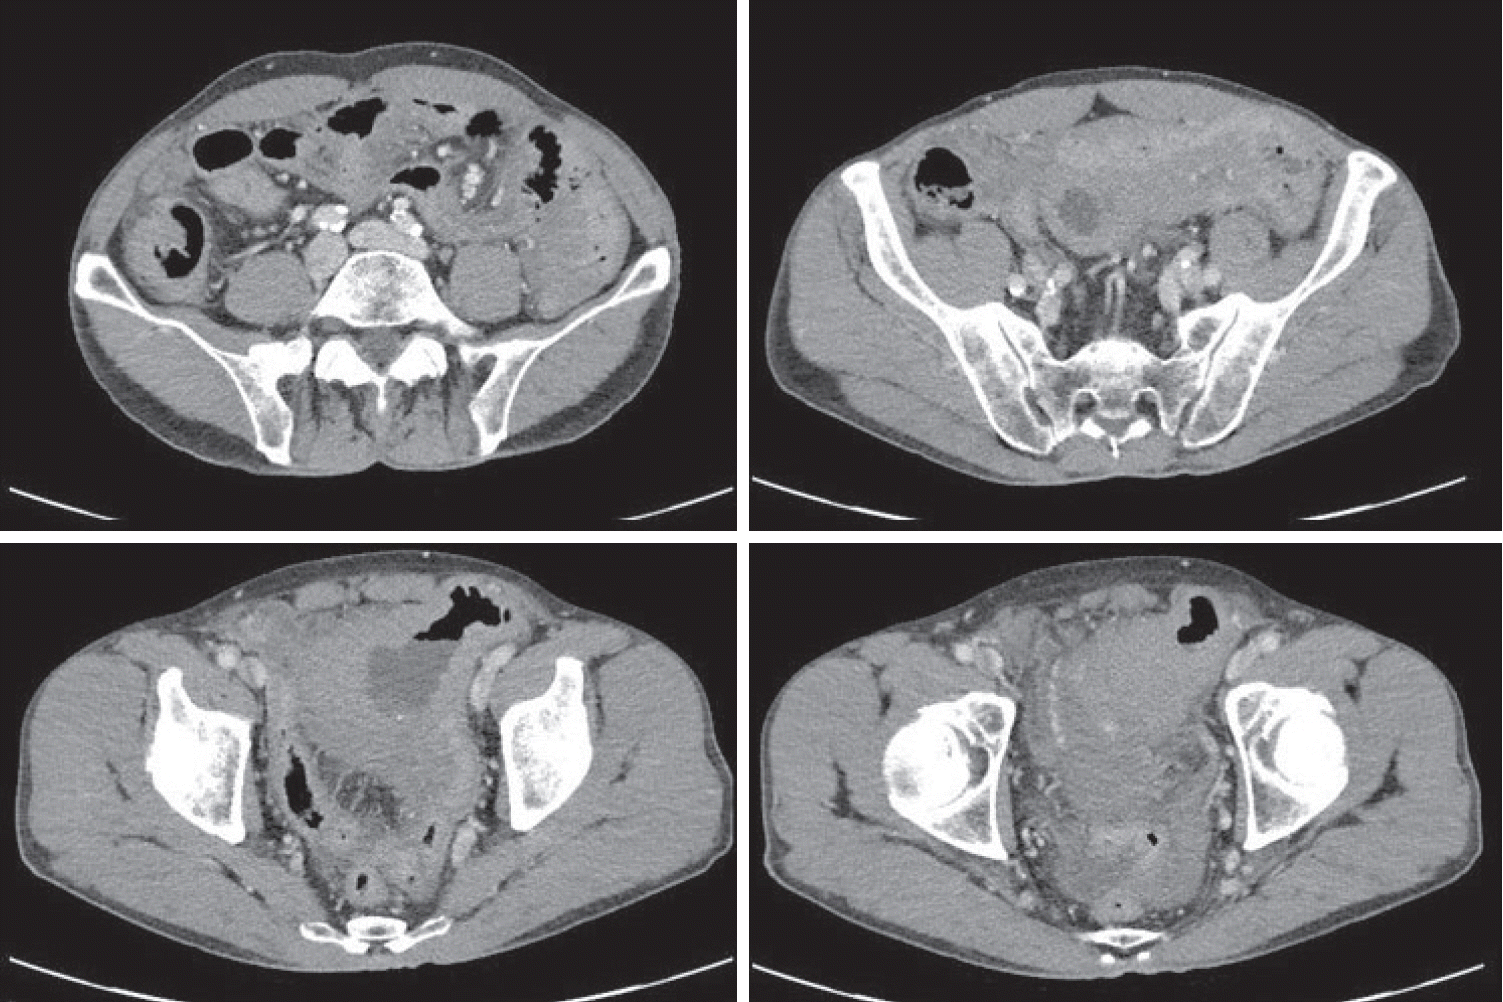

Figure 2.

Initial colonoscopy showing an irregularly shaped gross margin of the ulcer.

Figure 3.

Colonoscopy showing a scarred sigmoid ulcer 30 cm from the anal verge, with apparent improvement compared to previous findings.

A 70-year-old male underwent sigmoidoscopy after a routine computed tomography (CT) examination, which showed thickening of the sigmoid wall (Fig. 1). Sigmoidoscopy revealed a colonic ulcer, and a biopsy was performed. The lesion was identified as a tubular adenoma; therefore, the patient was referred to the gastroenterology department for repeat biopsy and additional tests. The patient’s medical history included high blood pressure and alcoholic hepatitis. His social history showed that he drank 0.5-1.0 bottle of soju daily and was never a smoker. Information regarding his family history was excluded from the study. The patient had no gastrointestinal symptoms such as abdominal pain or diarrhea, and physical examination findings were unremarkable. Although the biopsy showed a tubular adenoma, the initial colonoscopy indicated that the gross margin of the ulcer was irregularly shaped (Fig. 2), raising suspicion for malignancy. Therefore, despite being asymptomatic, the patient was informed, and another colonoscopy was performed 2 months later. The follow-up examination revealed a scarred sigmoid ulcer located 30 cm from the anal verge, which seemed to have improved compared with the previous findings. Re-biopsy demonstrated features consistent with a simple ulcer (Fig. 3). Accordingly, we concluded that this was a benign colonic ulcer with an inflammatory and ischemic cause rather than cancer, and a follow-up CT scan was sche-duled 1 month later. At the follow-up visit 1 month later, the patient complained of abdominal discomfort after eating for a week, which had not occurred before. He denied having fever, chills, nausea, or vomiting. A subsequent abdominal CT scan showed an approximately 9-cm cavitary lesion abutting the sigmoid colon and urinary bladder dome in the small intestine (Fig. 4). This was accompanied by diffuse nodular omentomesenteric infiltration and peritoneal thickening with small ascites. Based on these findings, the patient was suspected to have a malignant tumor, such as scirrhous carcinoma, inflammatory bowel disease, peritoneal carcinomatosis, or peritonitis, and was referred to a surgeon for surgical treatment. The patient was hospitalized immediately. On admission, the patient complained of abdominal discomfort after eating, and mild generalized abdominal tenderness was noted on physical examination. He was hemodynamically stable. Laboratory testing revealed high white blood cell count of 11.45 × 103/μL (normal range, 4.0-10.0 × 103/μL) with a differential of 67.6% neutrophils (normal range, 38.0-75.0), normal hemoglobin of 16.1 g/dL (normal range, 13.0-17.0), normal platelet count of 151 × 103/μL (normal range, 150-400 × 103/μL), and slightly elevated C-reactive protein level of 7.69 mg/L (normal range, 0.0-5.0). Serum electrolyte and kidney function test results were normal. On the 3rd day of hospitalization, the patient underwent laparoscopic small bowel resection. Immunohistochemical analysis of the resected tissue showed positive staining for CD3, CD4, CD8, CD56, and CAM 5.2 (epithelial marker), and a negative staining for CD10, CD20, CD21, and CD30 (Fig. 5). Histopathological evaluation revealed infiltration by small- to medium-sized T-cell with prominent epitheliotropism, consistent with MEITL. The final diagnosis was MEITL, involving the sigmoid colon, urinary bladder, and peritoneum. Postoperatively, the patient developed persistent ileus with progressive ab-dominal distension and loss of bowel passage, necessitating a second emergency surgery on the 20th day of hospitalization. On the 25th day of hospitalization, the Hemovac drainage became purulent, blood pressure decreased, and the patient went into shock; therefore, a third emergency surgery was performed under the suspicion of bowel perforation. On the 45th day of hospitalization, the patient died of refractory septic shock, presumed to be a complication of intestinal perforation.